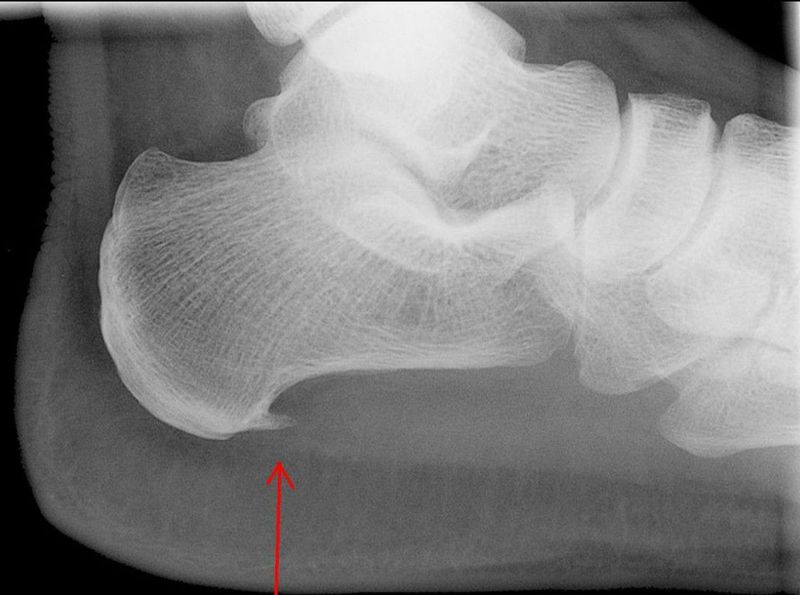

The fibrous layer of periosteum is sometimes described as LIMITING MEMBRANE , Based on observation that if periosteum is torn ,the osteogenic cells extend into surrounding tissues and form bony projections there(EXOSTOSES),which is frequently evident in old people